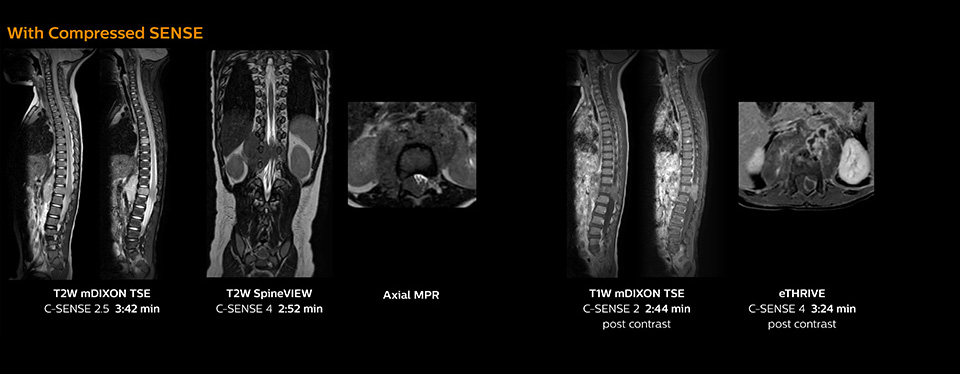

The KCH team has already changed most of their Ingenia 1.5T spine ExamCards by incorporating Compressed SENSE into their 2D TSE, mDIXON TSE, FFE, and 3D sequences.

“Previously with SENSE, our 2D mDIXON TSE scans required relatively long scan times. But now, with Compressed SENSE, we have reduced these scan times while maintaining a high SNR, because the Compressed SENSE technology helps reduce noise,” says Dr. Koyama.

“Because the faster scanning with Compressed SENSE saves us time, we can sometimes add a sequence to obtain high quality spine images in the same time slot for confident diagnoses. And in cervical spine exams, a 2D sequence is sometimes replaced by a 3D protocol, which provides us more information as it can be reformatted in different orientations. Compressed SENSE allows us to easily add this 3D sequence in the timeslot,” says Fukushima

“Incorporating Compressed SENSE in common spine sequences, such as mDIXON, 3D SpineVIEW and eTHRIVE, can substantially reduce the scanning time of these sequences, while maintaining adequate spatial resolution, resulting in high quality, multiple contrasts, multiple orientations,” says Dr. Koyama.

Pediatric spine with neuroblastoma

This 6-year-old patient with neuroblastoma underwent MRI on the Ingenia 1.5T. Compressed SENSE was used to reduce scan time while maintaining the high resolution for 2D mDIXON, 3D SpineVIEW and e-THRIVE in this case. The highly detailed images allowed the radiologist to make a quick and confident assessment of the position of the nerve and the tumor. Especially important for a pediatric patient, is that a shorter scan time also allows us to keep the sedation time as short as possible.

As this was one of the first patients scanned with Compressed SENSE, 3D SpineVIEW was acquired with and without Compressed SENSE to allow comparison. Although the Compressed SENSE sequence was significantly faster, the acquired and reconstructed 3D SpineVIEW images show virtually the same image quality.